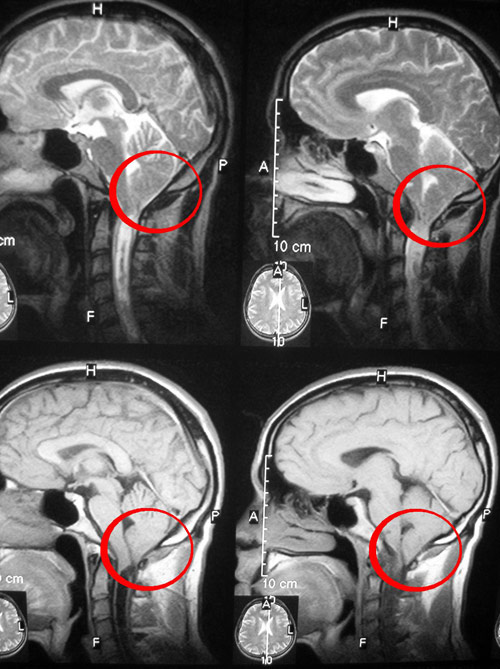

Синдром Арнольда-Киари - это аномалия развития головного мозга, при которой отдел черепа, содержащий мозжечок, является слишком маленьким или деформированным, вследствие чего происходит сдавливание мозга. Самая нижняя часть мозжечка или миндалины смещены в верхнюю часть позвоночного канала. Педиатрическая форма - синдром Арнольда-Киари III типа - всегда ассоциируется с миеломенингоцеле (грыжа спинного мозга и мозговых оболочек). Взрослая форма - синдром Киари I типа - развивается из-за недостаточно большой задней части черепа.

Когда мозжечок вдавливается в верхнюю часть позвоночного канала, он может препятствовать нормальному оттоку ликвора, который защищает головной и спинной мозг. Нарушенная циркуляция ликвора может привести к блокаде сигналов, передаваемых от головного мозга к нижележащим органам или к скоплению спинномозговой жидкости в головном мозге и спинном мозге. Давление мозжечка на спинной мозг или нижнюю часть ствола мозга может вызвать сирингомиелию.

Если вы страдаете от головной боли, но причина этого симптома не ясна для врача, вас попросят пройти магнитно-резонансную томографию (МРТ), которая поможет выявить, есть ли у вас аномалия Киари.

Иногда перед обследованием необходимо ввести контрастное вещество, с помощью которого, при его попадании в мозг, повышается контрастность и четкость изображения. МРТ – это безопасный и безболезненный метод. В последующем с помощью повторной МРТ можно будет вести мониторинг прогрессирования этого заболевания.